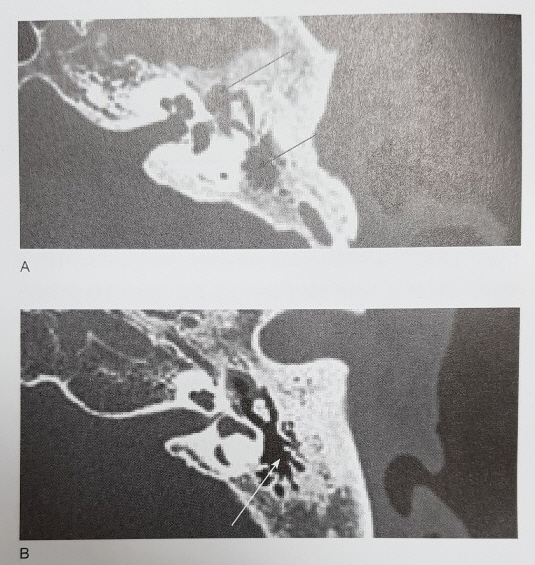

[그림설명] 만성 중이염 환자들에서의  측두골 전산화단층촬영

첫 번째 환자(A)에서는 중이와 유양돌기가 염증조직(화살표)으로 채워져 있고, 다른 환자(B)에서는 고막 천공만 있으나 유양돌기는 염증조적이 없이 비교적 환기가 잘 되어 있습니다. 귀 안쪽에 있는 보이지 않는 구조물에 염증이 있는지 확인하기 위해 전산화단층촬영이 필요한 경우가 많습니다.